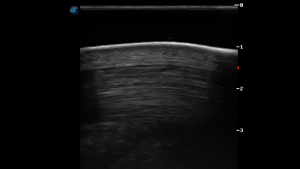

SIMON Ultrasound Database

This ultrasound database is a free resource for students and doctors!

Our collection includes videos of dogs, cats, horses, cows, humans, and many other species!